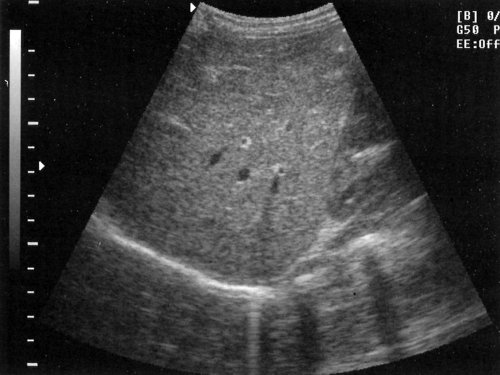

Поперечный срез печени

Поперечный срез печени может быть получен поворотом датчика на 90° от продольного положения и проведением его через печень (рис. 9). Эти срезы значительно помогают при оценке дилатации внутрипеченочных желчных протоков, которая отчетливо видна на поперечных срезах правой доли.

Рис. 9. Получение поперечного среза печени.а) Схема наложения датчика для получения поперечного среза печени.б) Поперечный срез здоровой печени (эхограмма).